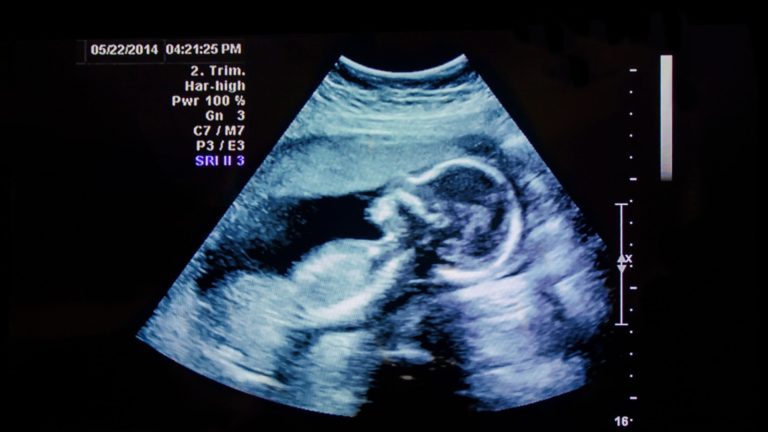

Saber leer ecografías de embarazo

Los procedimientos de ecografía se realizan por una variedad de razones. Una de las aplicaciones más comunes es verificar el desarrollo de un bebé durante el embarazo. Las pruebas de ecografía son muy seguras durante una etapa tan importante en la vida de una persona porque, a diferencia de los rayos X, no penetran los huesos. En lugar de usar radiación, las ecografías utilizan ondas sonoras o ecos para crear imágenes del feto o bebé.

Ubica tu bebé

Lo siguiente a notar durante las interpretaciones de ecografías es el bebé. Se verá de color gris o blanco en la imagen. Estará ubicado dentro del área más oscura de la imagen, que es el líquido amniótico. La cantidad de detalles que puedes ver dependerá del estado del embarazo y del desarrollo del bebé. Algunas de las cosas que podrías reconocer incluyen:

- Semana 8 de embarazo: Verás una imagen de un feto que parece tener el tamaño de una alubia (frijol).

- Semana 12 de embarazo: La imagen de la ecografía mostrará claramente la cabeza del bebé.

- Semana 20 de embarazo y más tarde: Podrás reconocer los pies del bebé, el corazón, los ojos, la columna vertebral y mucho más.